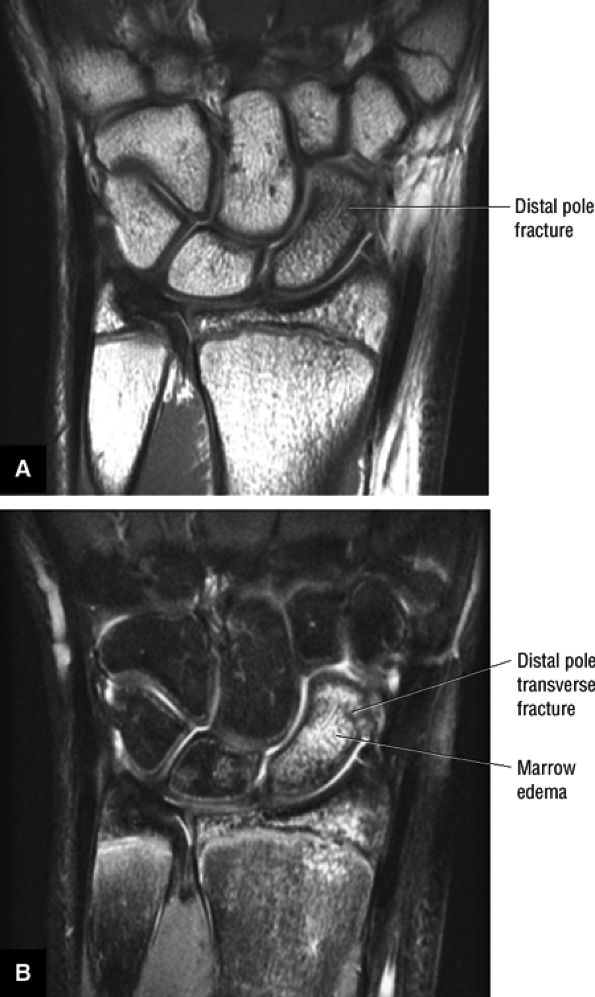

FIGURE 10.91 ● (A) T1-weighted and (B) STIR coronal images of a chronic avulsion fracture of the ulnar aspect of the scaphoid. The scapholunate ligament (straight arrow) is still attached to both the lunate and the surface of displaced scaphoid fracture fragment (curved arrow). S, scaphoid; L, lunate.